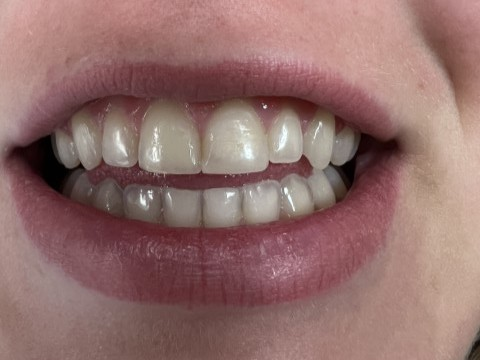

Anterior broken tooth. Double DentXpinTM repair.

4